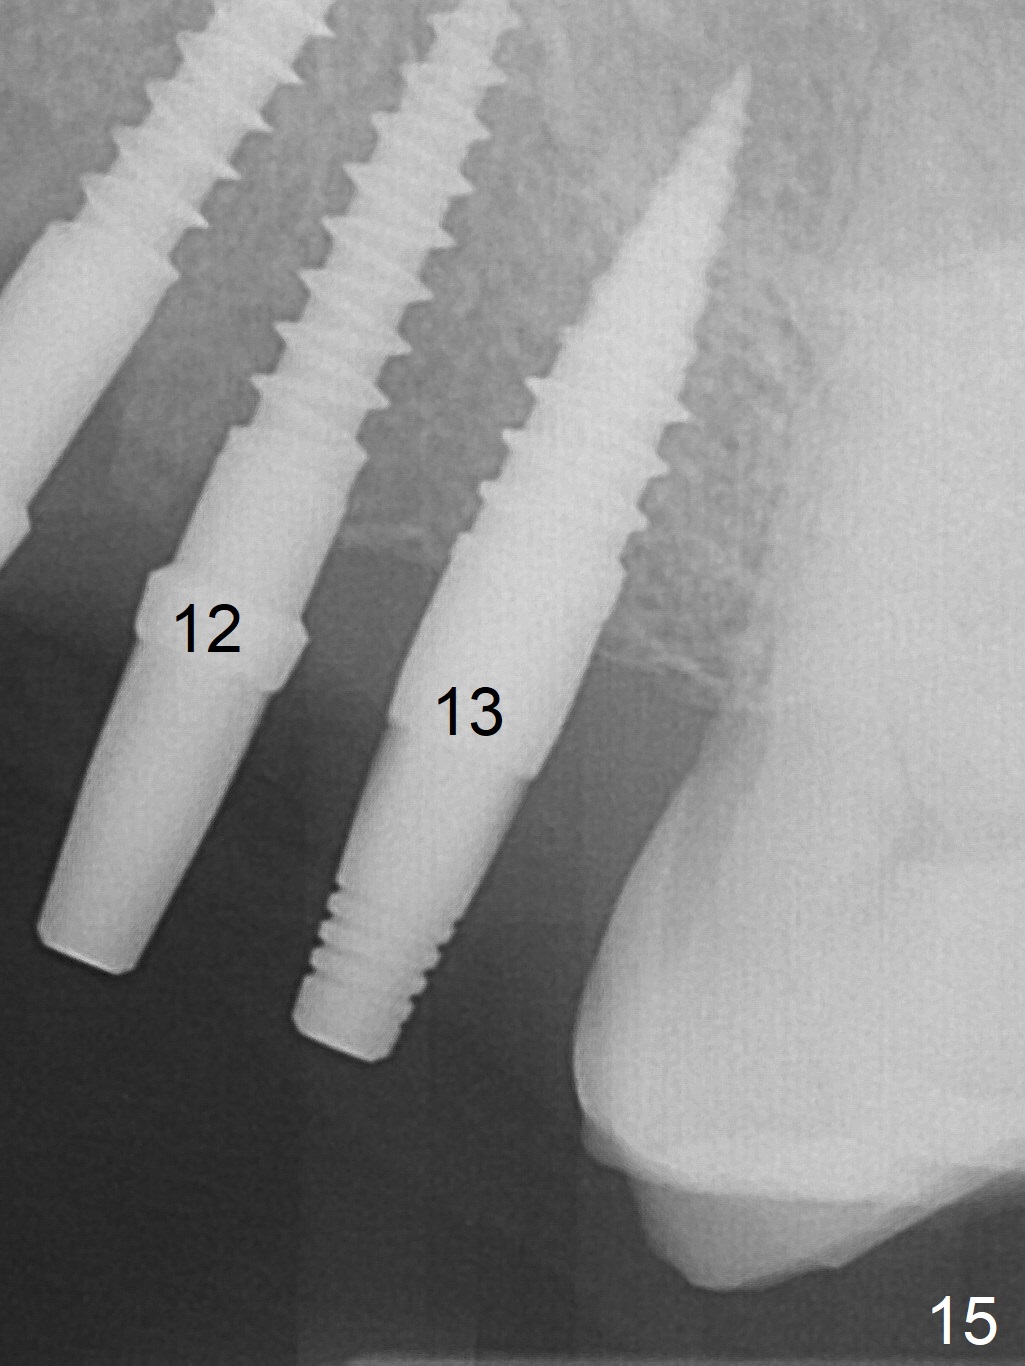

At the sites of #11 and 12, the knife-edged ridge is trimmed prior to initiation of osteotomy (Fig.12,13). With the flattened ridge, it is easy to start osteotomy and control the mesiodistal position. When the position and the trajectory are not correct, they can be changed (Fig.14-16) with 2.5x14(4), 2.5x12(2) and 3x10(2) mm implants placed at #11,12, and 13, respectively. With relatively correct position of each implant, it would be easy to fabricate a splinted 6-unit provisional.